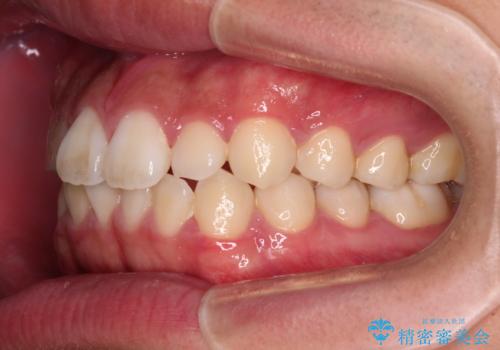

- 上下前歯の叢生を気にして来院された患者様です。

費用を抑え、期間もあまりかけずに治療をしたいとのことで、インビザライン・ライトを用いて矯正治療を行うこととしました。

インビザライン・ライトは、製作できるアライナーの枚数に制限があるため、移動可能な量に限りがあります。

一方で、半年から1年程度で治療を終えることができるため、軽度の歯列不正の患者様には大変お勧めです。